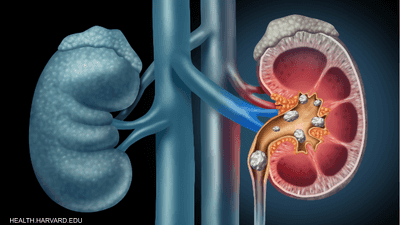

طوّر باحثون من جامعة تارتو في إستونيا أداة قائمة على الذكاء الاصطناعي قادرة على تسريع الكشف عن سرطان الكلى وتحسين دقة تشخيصه، وفق دراسة علمية نُشرت في مجلة “Communications Medicine”.

وتعتمد الأداة، التي تحمل اسم “BMVision”، على تقنيات التعلم الآلي لتحليل صور التصوير المقطعي المحوسب (CT)، ومساعدة أطباء الأشعة على اكتشاف الآفات الخبيثة والحميدة بشكل أسرع وأكثر موثوقية، بما في ذلك الحالات التي لم تُجرَ فيها الفحوصات أصلا بغرض البحث عن الأورام.

وأظهرت النتائج أن استخدام الأداة المدعومة بالذكاء الاصطناعي قلّص الزمن اللازم لتحديد وقياس والإبلاغ عن الأورام الخبيثة بنحو الثلث، مع تحسن ملحوظ في دقة القياس والتوافق بين الأطباء.

من جهتها، أوضحت أستاذة الأشعة بمستشفى جامعة تارتو، الدكتورة بيلفي إلفيس، أن إدخال هذه الأداة قد يسهم في تحسين جودة التشخيص والكشف المبكر عن سرطان الكلى، مشيرة إلى أنه “رغم استخدام الحل إلى حدود الآن لأغراض بحثية فقط، فإنه يجري حاليا دمجه ضمن سير العمل السريري، على أن تتم معالجة جميع فحوصات التصوير المقطعي للبطن مستقبلا عبر نظام BMVision”.

هذا وحصلت أداة “BMVision” على علامة المطابقة الأوروبية (CE)، ما يؤكد استيفاءها لمعايير السلامة والصحة والبيئة المعتمدة في المنطقة الاقتصادية الأوروبية، لتصبح بذلك أول أداة ذكاء اصطناعي متاحة في السوق تساعد على الكشف المبكر عن سرطان الكلى وتقييمه بدقة أعلى.